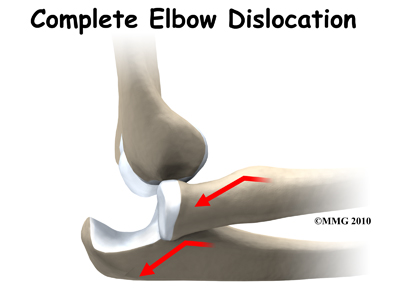

When the joint surfaces of an elbow are forced apart, the elbow is dislocated. The elbow is the second most commonly dislocated joint in adults (after shoulder dislocations). Elbow dislocations can be complete or partial. A partial dislocation is referred to as a subluxation. The amount of force needed to cause an elbow dislocation is enough to cause a bone fracture at the same time. These two injuries (fracture-dislocation) often occur together.

When the joint surfaces of an elbow are forced apart, the elbow is dislocated. The elbow is the second most commonly dislocated joint in adults (after shoulder dislocations). Elbow dislocations can be complete or partial. A partial dislocation is referred to as a subluxation. The amount of force needed to cause an elbow dislocation is enough to cause a bone fracture at the same time. These two injuries (fracture-dislocation) often occur together.

What are the symptoms? If the elbow is fully dislocated, it will look out of joint. There may be dimples or indentations of the skin over the dislocation where the bones have shifted position. Pain can be intense until the arm is relocated. The pain is often significantly relieved immediately after the joint is put back in place but there will be residual tenderness around the joint.

If the elbow is fully dislocated, it will look out of joint. There may be dimples or indentations of the skin over the dislocation where the bones have shifted position. Pain can be intense until the arm is relocated. The pain is often significantly relieved immediately after the joint is put back in place but there will be residual tenderness around the joint.

It is possible for the elbow to relocate by itself. This is more likely when there is a subluxation, rather than a complete dislocation. Sometimes a trained medical person can reduce the elbow by applying a quick motion to the forearm. There are several different methods used for manual (closed) reduction. Closed reduction refers to the fact that the elbow can be put back in joint without surgery. An open incision is not needed.